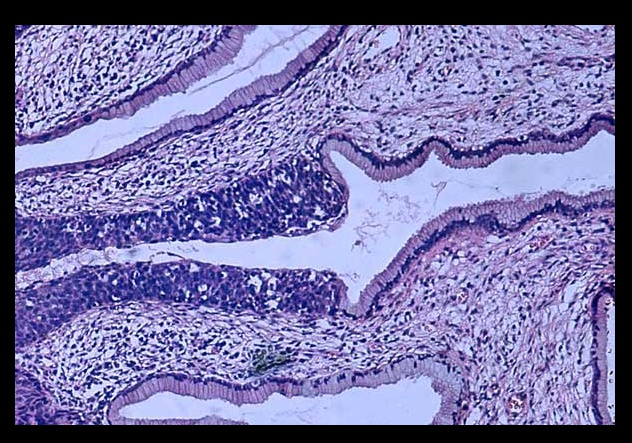

High grade dysplasia (carcinoma in situ) in the uterine cervix. The abnormal epithelium is extending into a mucus gland to the left of centre. This disease can progress to invasive cancer (squamous cell carcinoma) of the cervix:

CIN III

Development of dysplasia and carcinoma of the cervix. Repeated human papillomavirus (HPV) infections convert normal epithelium (left) into increasingly severe dysplasia until malignant epithelium breaks through the basement membrane to become invasive cancer‚ capable of metastasis by invasion of blood vessels and lymphatics.

_CIN I to III can regress. CIS cannot regress and will proceed to invasive squamous cell carcinoma once it breaks through basement membrane.

_Carcinoma in situ is characterized by atypical changes extending through the entire thickness of the epithelium.

As it has not yet invaded the basement membrane, it is considered a precancerous lesion.